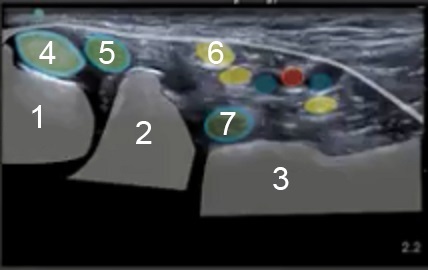

1. Medial Malleolus of the Tibia

2. Talus

3. Calcaneus

4. Posterior Tibialis Tendon

5. Flexor Digitorum Longus

6. Medial Nerve

7. Flexor Hallucis Longus

Blue Dots: Veins

Red Dot: Artery